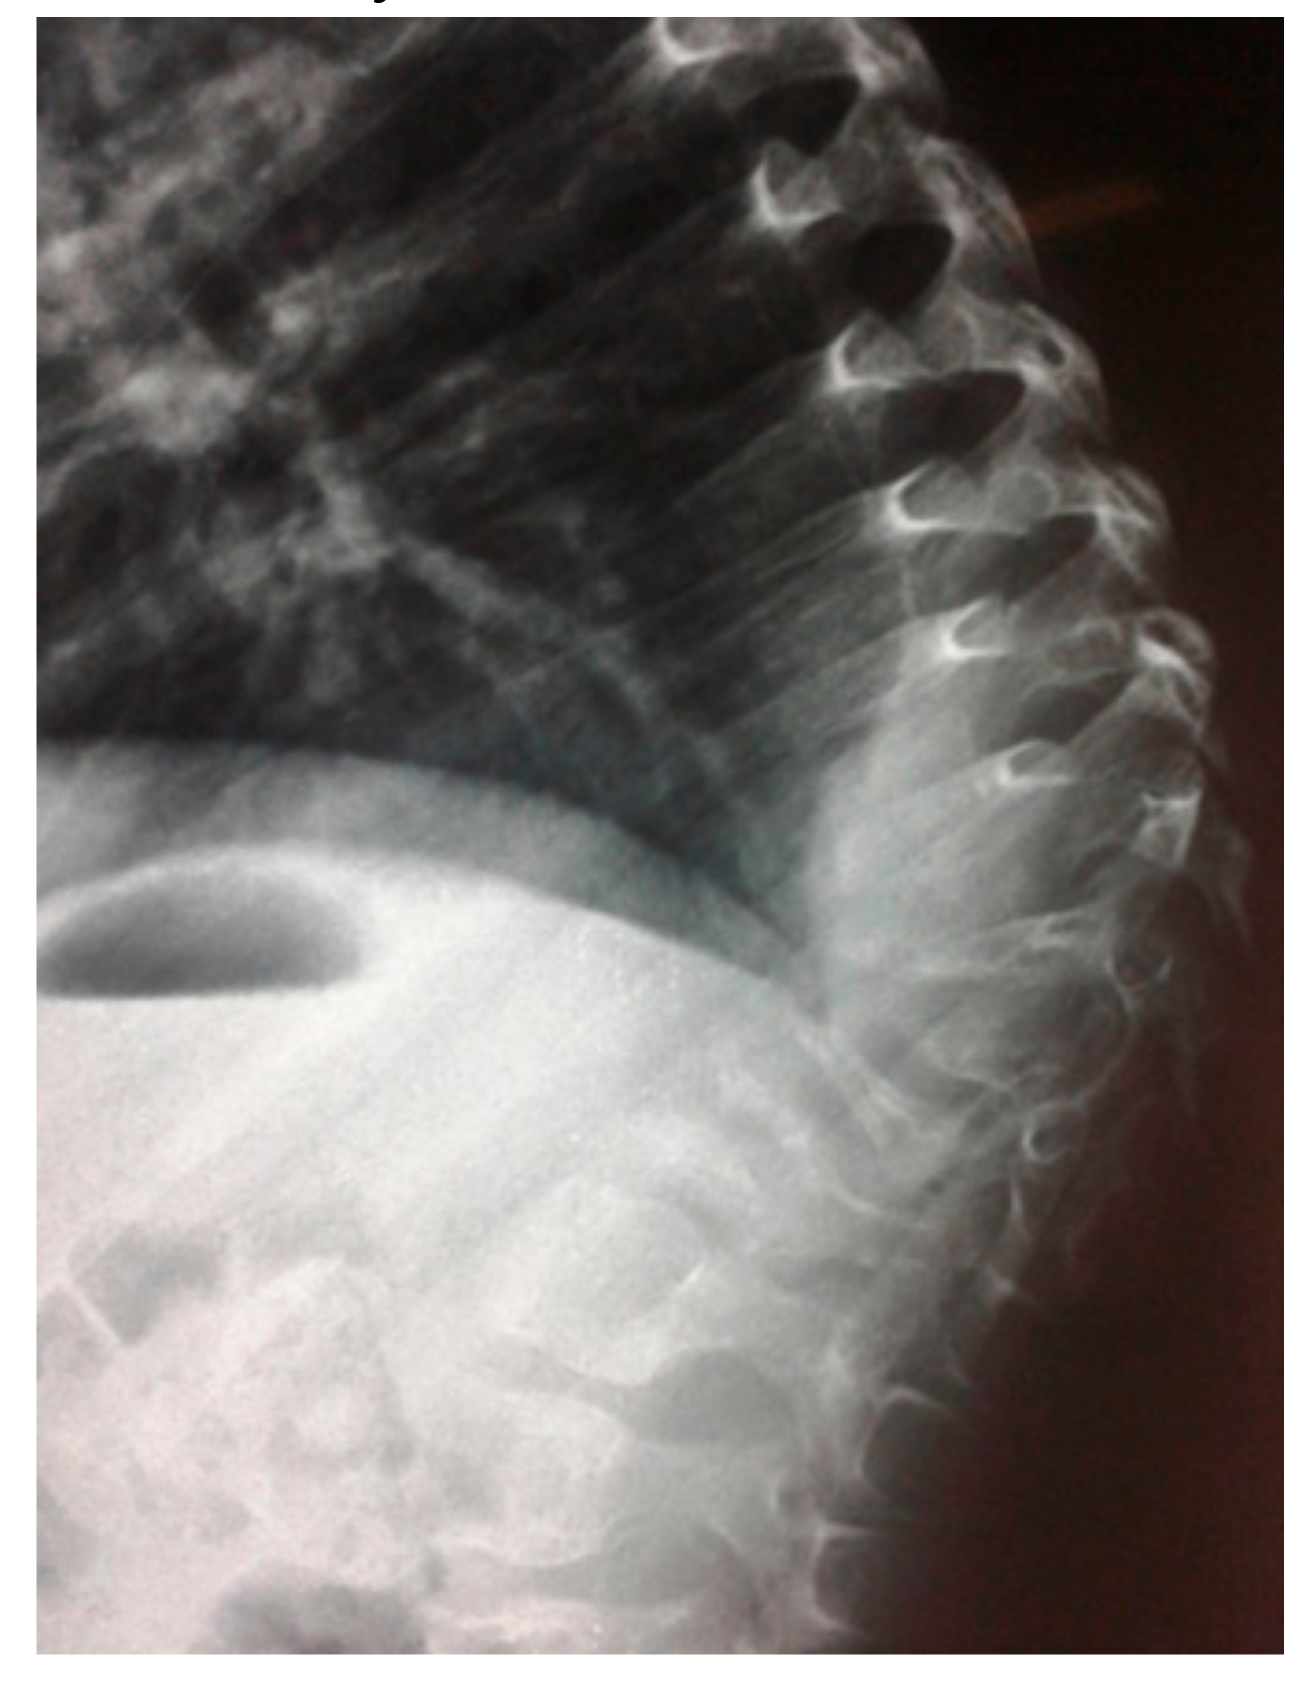

- A seven-year-old-boy was seen for the first time at the age of three years because of painful thoraco-lumbar kyphosis resulted from osteolysis of T9-L1. The left iliac crest was also involved in the pathological process of osteolysis (Figure 1). Back pain associated with Trendelenburg gait were the most bothersome symptomatology. Bone biopsy confirmed the diagnosis of Gorham-Stout disease. The kyphosis has been treated by a brace. Follow-ups showed stability of the kyphosis and dormancy of the osteolysis.